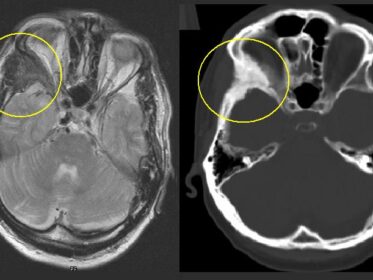

Displasia fibrosa: clinica, diagnosi e trattamento

La displasia fibrosa è un tumore osseo benigno, raro e di natura congenita, descritto per la prima volta da Von Recklinghausen nel 1891. La sua caratteristica fondamentale è la sostituzione del normale tessuto osseo con tessuto connettivo fibroso, anche noto come tessuto cicatriziale. Questa alterazione strutturale indebolisce l’osso interessato, rendendolo più suscettibile a deformità e…